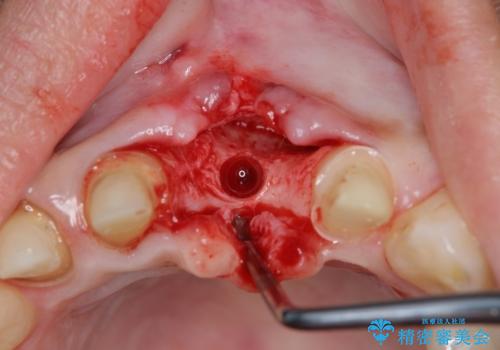

左側の前歯には他院で埋入されたポジションの悪いインプラント補綴により歯冠長の長いクラウンが装着されており、感染による排膿も認められこのまま審美性を改善するのは難しい状態です。

不良インプラントを除去し最終的にブリッジによる補綴で審美性の改善を行うこと、その準備として骨の造成・歯肉の移植による歯の欠損部顎堤のボリュームを維持・増大を計画します。

感染したインプラントからは排膿が間欠的に認められ、掻爬・除去が検討されうるような状況でした。

より審美的な改善を強く求められたため、インプラントを除去し可及的に欠損部顎堤を増大したのちブリッジによる審美改善を行いました。